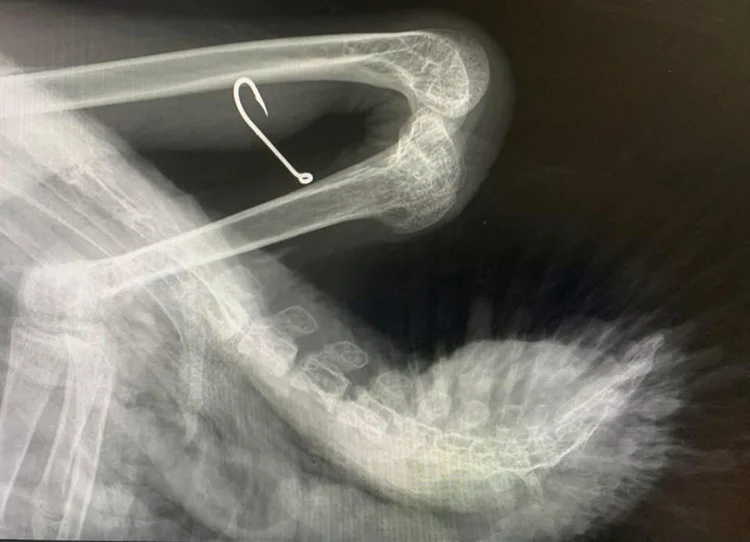

Så langt har vi reddet et stort antall svaner og andre fuglearter – og behovet er økende. Fremover ønsker vi også å oppgradere mottaket vårt, blant annet med en egen badedam i en trygg, inngjerdet innhegning. Nå nærmer hekketiden seg, og vi vet at både voksne svaner og svaneunger vil trenge hjelp – ofte som følge av menneskelig aktivitet.